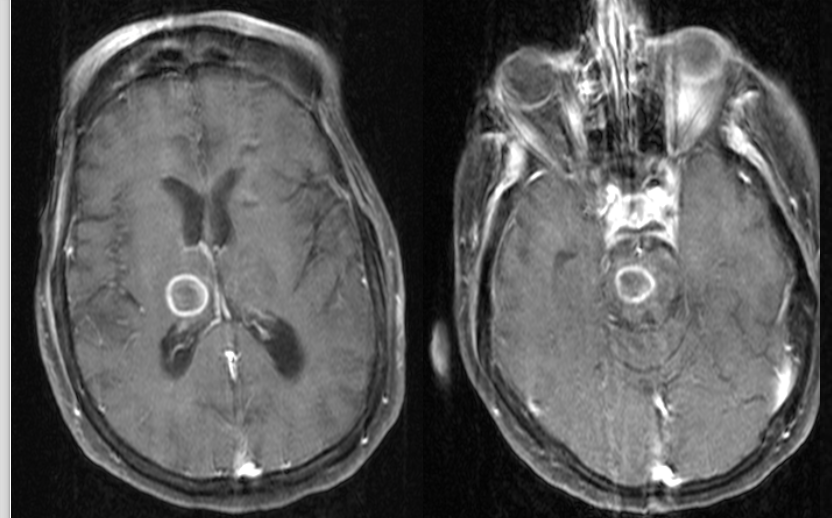

A 56 year-old immunocompromised man presented with seizures.

Aspergillosis

Imaging

A 34 year-old man from Mexico presented with a long history of seizures.

Neurocysticercosis